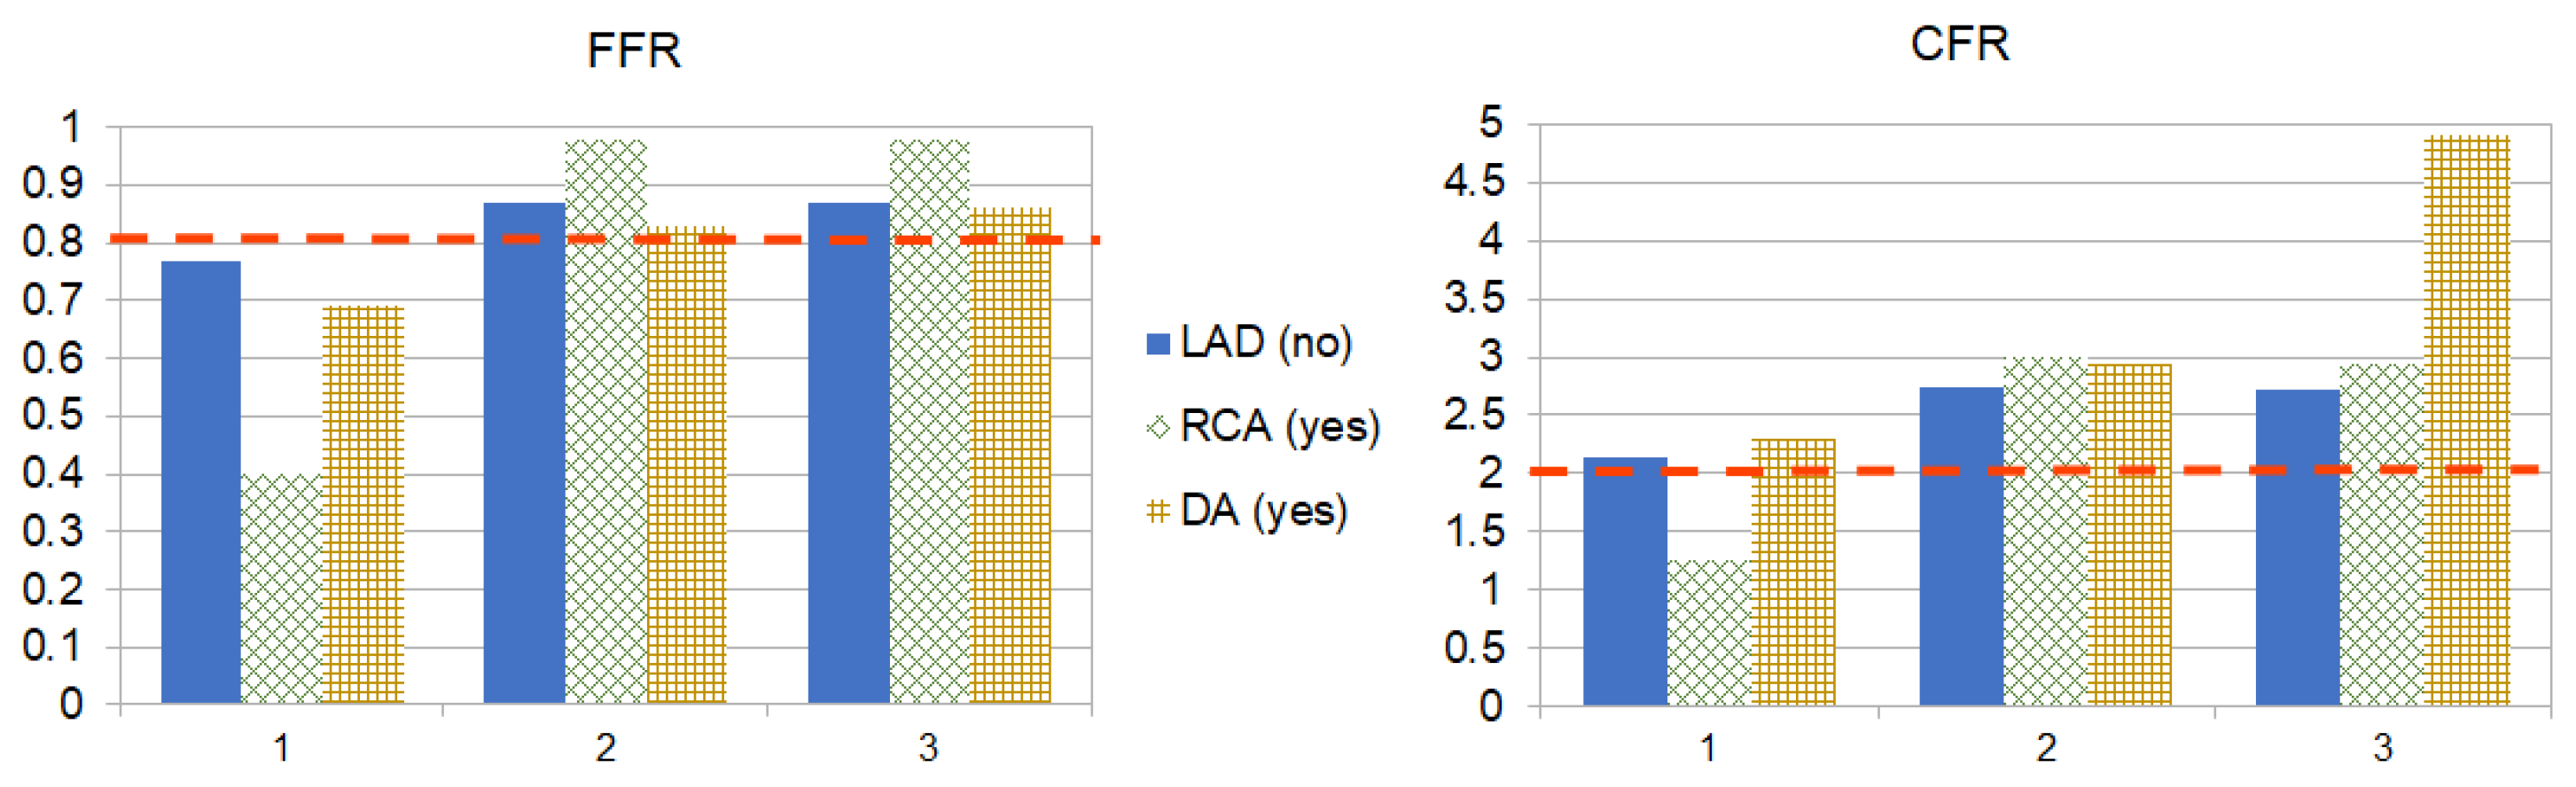

4. Results

5. Discussion